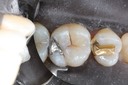

Joe Cha #29 die

Joe Cha #29 finish